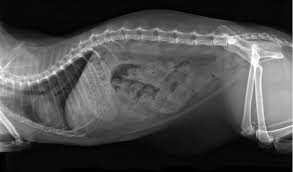

Megacolon is a condition in which the colon becomes abnormally dilated & enlarged losing its ability to contract, we take a look at this disorder in cats. Constipation is a common problem in cats. Vet clin north am small anim pract. It happens when the large intestine is filled with fecal matter which causes it to enlarge beyond its normal diameter. Most cats respond well to medical therapy and diet change and do not need advanced procedures.

Vet433b Lec 31 Feline Constipation Hulsebosch Nd Flashcards Quizlet from o.quizlet.com This cat was obviously being given the wrong treatment for megacolon. This relatively common colonic disorder usually occurs idiopathically (without a known cause), secondary to chronic constipation and obstipation. They don't stimulate the muscle to most of the time, medical therapy of megacolon is attempted first. Megacolon is a severe cause of constipation. This can help the cat to eliminate feces. Causes of megacolon in cats. Megacolon is much more common in cats than dogs. Feline megacolon, which is a generalized dysfunction of colonic smooth muscle, is characterised by a chronic history of constipation and a dilated and hypertrophied colon.

The veterinarian may use enemas, laxatives, stool softeners, and a high fiber diet. Megacolon in cats literally means enlarged colon. Megacolon is a relatively common gastroenteric disorder in cats, and certain breeds such as siamese appear to be predisposed. Megacolon can be a frustrating disease for veterinarians, owners, and, most importantly, for the affected cats. He was prescribed lactulose with only mild improvement. And then, there's the dreadful enema. This condition is called megacolon. Feline megacolon requires constant treatment. I'm hoping between meds & a high fiber diet she'll be okay. Some cats with megacolon do well with the addition of fiber (bran, pumpkin, metamucil) while other cats do better with a prescription. Feline megacolon, which is a generalized dysfunction of colonic smooth muscle, is characterised by a chronic history of constipation and a dilated and hypertrophied colon. Cats with megacolon have lost their ability to move stool through the large intestine. Special diets are often recommended during the recovery period (usually something highly digestable to minimize the amount of stool produced).